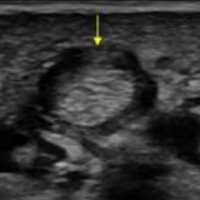

Trigger finger is a type of stenosing tenosynovitis. It develops due to repetitive microinjury from frequent flexion-extension movements of the fingers.

Primary trigger finger occurs most commonly in the middle fifth to sixth decades of life and up to 6 times more frequently in women than men.

A patient with trigger finger finds it difficult to straighten or bend the affected finger. The finger transiently gets locked in the flexed position and with a painful snapping sensation goes into extension.

Thickening and hyper-vascularization of the A1 pulley are the hallmarks of trigger fingers on sonography. Other frequently observed features include distal flexor tendinosis and tenosynovitis.

The first annular pulley (A1) at the metacarpal head is by far the most often affected pulley in trigger finger, though cases of triggering have been reported at the second and third annular pulleys (A2 and A3, respectively), as well as the palmar aponeurosis.

The level of thickening can be variable with some authors suggesting the normal value being around 0.5 mm with thickening suggested when the diameter is over 1.1 mm.

The condition can be conservatively managed with splinting, NSAIDs, and local steroid injections or may require a surgical section of the A1 pulley when the pulley is markedly thickened.